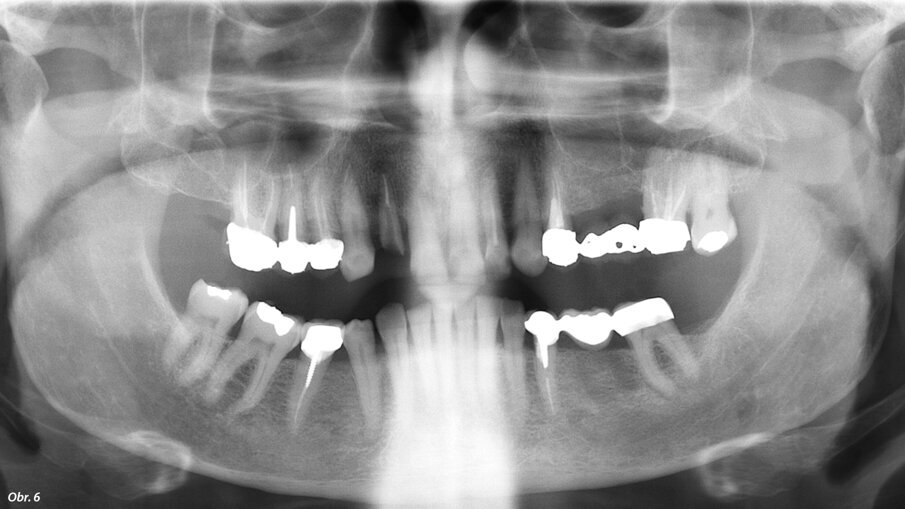

66letý pacient s non-inzulin dependentním diabetes mellitus a ischemickou chorobou srdeční se dostavil na ošetření parodontálního abscesu v oblasti radix relicta 12 a vícečetných fraktur stávajících náhrad (obr. 1–6). Během návštěvy byla zjištěna značná malokluze a ztráta VRO, abraze a fraktury stávajících náhrad i zbylých zubů a známky cervikální abfrakce. Pacient také trpěl mírnou bolestivostí svalů při palpaci, a to zejména v oblasti m. pterygoideus medialis et lateralis, sníženou schopností otevírání úst a slabými zvukovými fenomény v oblasti temporomandibulárních kloubů.